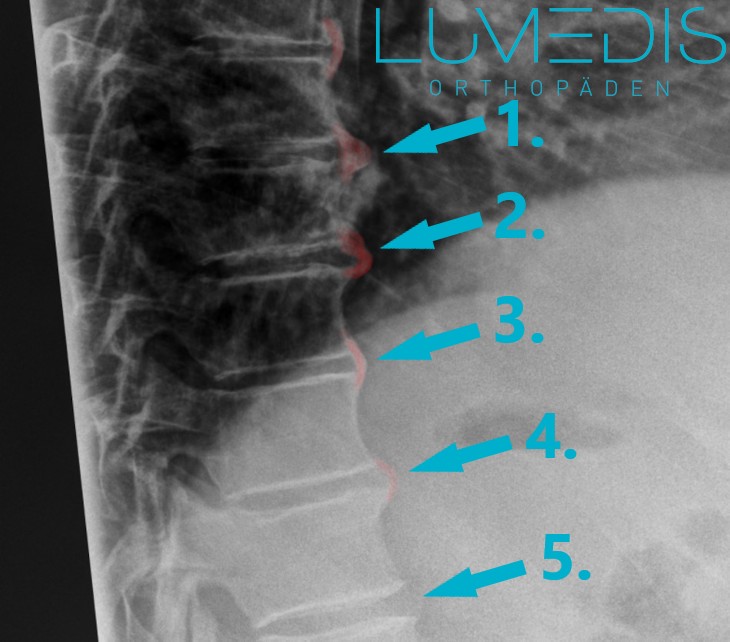

Röntgenbild der LWS mit Wirbelgleiten (Meyerding 1°)

Die türkise Linie zeigt jeweils die Hinterkanten der Wirbelkörper.

Die rote Linie zeigt das jeweilige Wirbelgleiten.